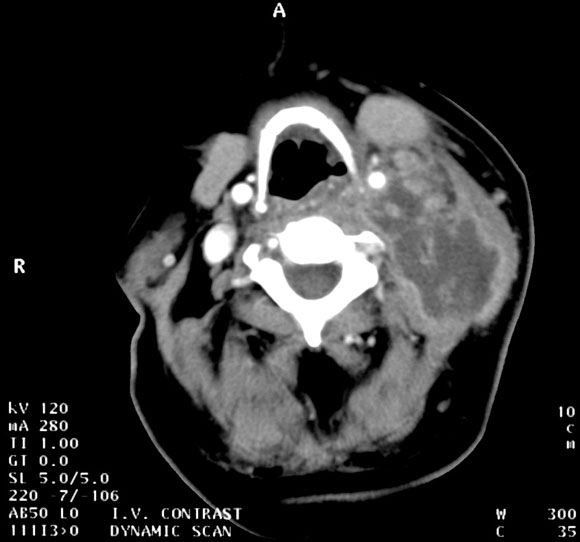

Presentation: A 14-year-old girl presented with a four-week history of progressive swelling in the left submandibular region. Despite treatment with oral flucloxacillin for 10 days she experienced increasing pain, fever and torticollis.

Management: The girl was admitted to hospital and given intravenous flucloxacillin and penicillin for three days without improvement.

Further history revealed that both the girl and her younger brother had experienced recurrent boils since a family visit to Samoa a year previously. Swabs of pus from a boil, as well as from her nose, axilla and groin, had failed to show any pathogens. The boils had responded slowly to flucloxacillin. Attempted eradication of staphylococci with intranasal mupirocin and triclosan washes had prevented further skin sepsis.

Investigations: Magnetic resonance imaging of the neck demonstrated necrotic submandibular lymphadenitis with a deep cervical abscess (right). The abscess was drained under anaesthesia. Culture of the pus revealed "community type" or "non-multiresistant" methicillin-resistant Staphylococcus aureus. The isolate was susceptible to erythromycin, tetracycline, gentamicin and ciprofloxacin, and resistant to β-lactams, flucloxacillin and cephalexin.

Management and course: Treatment was changed to clindamycin. Over the next 24 hours, the fever abated, and within seven days the swelling and pain decreased. Therapy was changed to oral clindamycin. After a further four weeks' therapy, the infection was completely resolved.

• Methicillin-resistant S. aureus (MRSA) is no longer confined to patients with a history of recent hospitalisation.

• "Community" MRSA strains are increasingly reported in children and are often associated with pyogenic complications.

• Failure to consider or recognise MRSA may lead to inappropriate β-lactam therapy. We believe that boils and furuncles should be swabbed for Gram stain and culture.